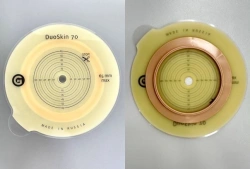

Medical product is intended for use in colostomies, ileostomies and urostomies for hermetic and secure attachment of stoma bags to the skin of the anterior abdominal wall, as well as to protect the skin of the peristomal area from stoma secretions and preserve the physiological functions of the skin due to the absorption of natural skin moisture (sweat, sebum).